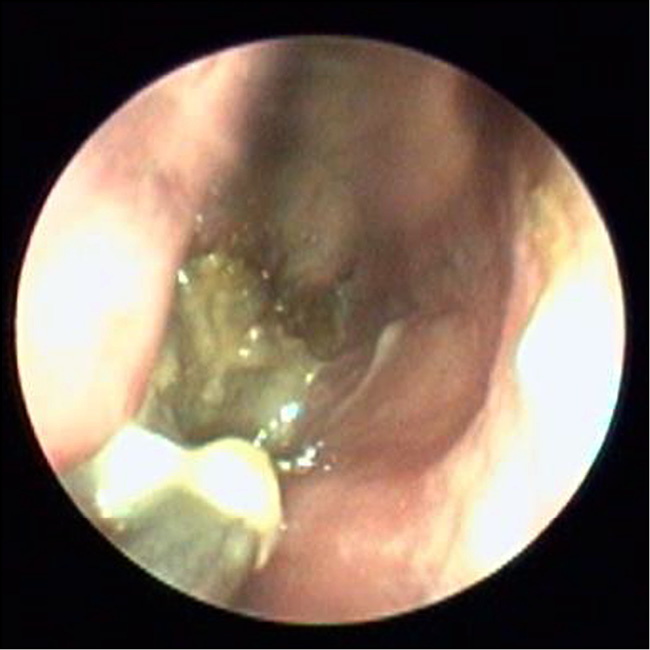

Первичный осмотр

С помощью прямого эндоскопа 0° осматривалась полость носа и носоглотки. Визуализировались участки множественного некроза средних и задних отделов перегородки носа, задних концов нижних носовых раковин и средние носовые раковины, медиальная стенка верхнечелюстной пазухи с костной деструкцией на стороне поражения, некротизированные ткани в области решетчатого лабиринта и медиальной стенки орбиты. При этом противоположная сторона могла быть не изменена. Типичная эндоскопическая картина представлена на рис. 3.

Рис. 3. Видеоэндоскопический осмотр полости носа